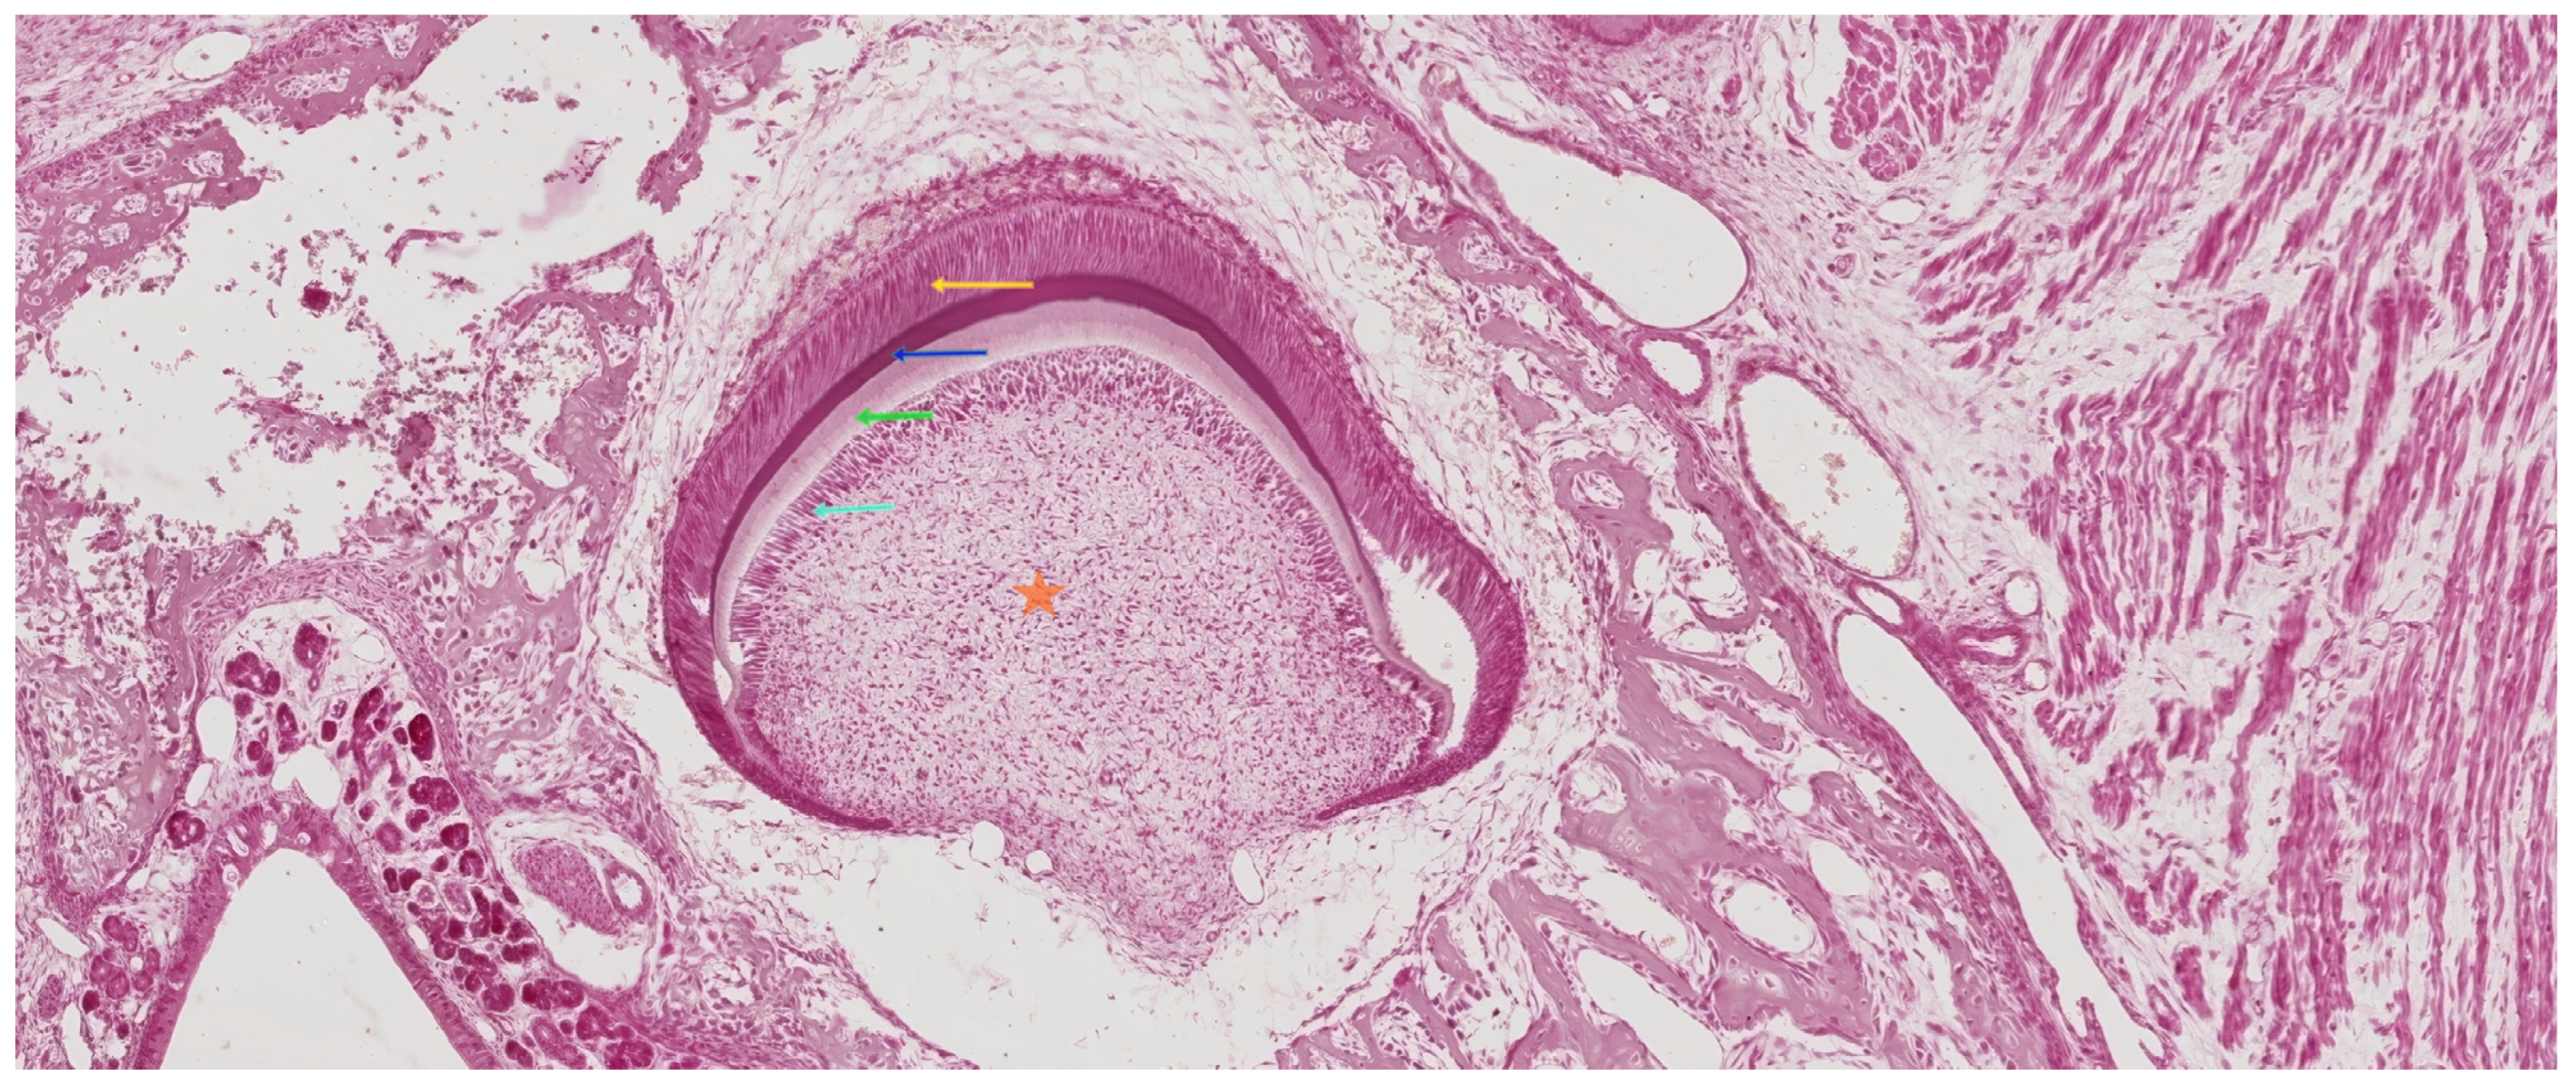

3.3. The Bell Stage

3.3.1. Early Bell Stage

3.3.2. Late Bell Stage

Differentiation of Odontoblasts

Differentiation of Ameloblasts